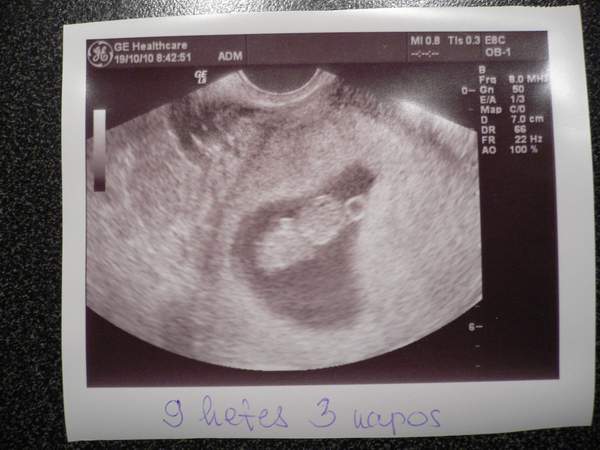

És akkor a kerek-fejű-gyerek :)

És egy kis magyarázat hozzá :)

A kép jobb oldala felé, az nem egy glória a feje felett, hanem a szikhólyag.. ami amellett van az a feje.. balfele meg a nagyobb gombóc a teste amin látni a kéz-kezdeményét... Én mondjuk a fején mintha 2 szemet is látnék.... :lol: :lol: :lol: :lol: :lol: